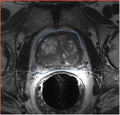

We will evaluate the applicability of the prostate segmentation tools developed by Georgia Tech (Yi Gao) on the 1.5T and 3.0T scans with and without endo-rectal coil.

• evaluate the accuracy of segmentation compared with the manual outlines (we will use the publicly available dataset from MICCAI 2009 Prostate segmentation challenge (1.5T) as well as the images from on-going image-guided biopsy program at BWH (3T T2w, Siemens Magnetom)

• Testing performed using the atlas constructed using MICCAI'09 challenge data (different field strength) for segmenting intra-procedural MRI w/o er-coil obtained at 3T